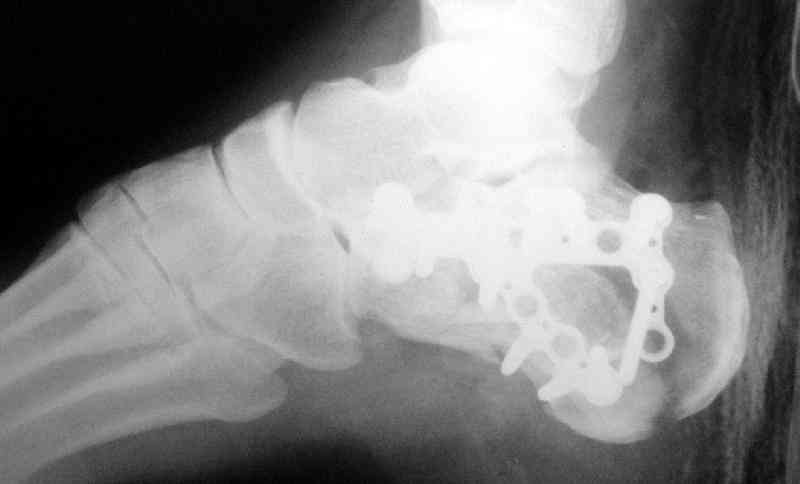

Пяточной пластиной

С уважением, А.Семенистый.

ГКБ № 13, Москва.

Открытый и закрытый способы лечения.

А хирург спит хорошо, когда пациенту хорошо, и ему не снятся его осложнения.

Имея какой-то опыт остесинтеза пяточной кости пластинами пришли к выводу - где есть альтернатива лучше без нее, где нет значит пластина и долгие переживания в ожидании очередной перевязки. Может нам так не везло, но и одного некроза( слава богу без остеомеилита) достаточно, чтобы призадуматься.